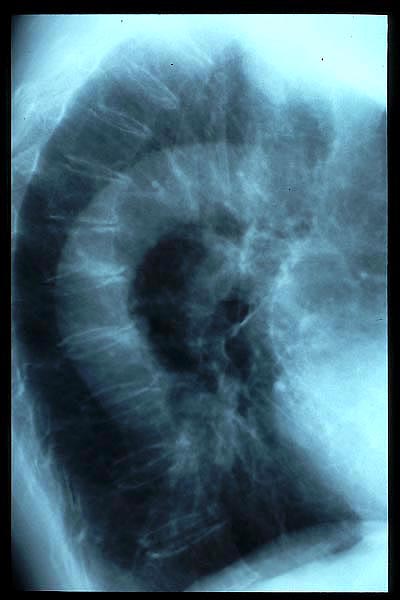

Diverticulosis de colon. Megacolon.